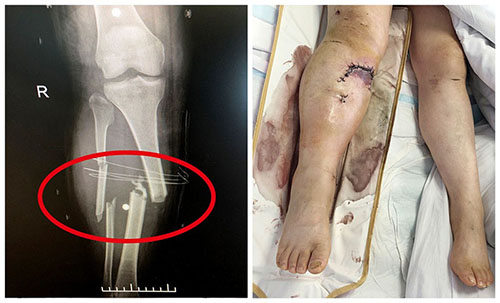

▲遭遇车祸的患者全身多处严重骨折

“脑挫伤、蛛网膜下出血、全身多处骨折、失血性休克……”当遍体鳞伤的文女士一被抬下救护车,就被紧急转入医院8楼重症病房。“经过格拉斯哥昏迷评分法(GCS)评估,患者得分为7分,属重度昏迷。”潘仁龙医生介绍,情况危急,他立即为患者进行气管切开手术,排除堵塞的污物,用呼吸机等设备维持住患者的呼吸心跳。当天给患者输血1200ml后,使其血压逐步稳定下来。

稳住后,如何选择较优治疗方案成为头等大事。潘仁龙邀请沪上知名三甲医院专家前来会诊后,形成了两套治疗方案——一是“先促醒,后接骨”,二是“先接骨,再促醒”。当时,外院专家倾向于第一种方案,认为先确认患者有机会从昏迷中苏醒,而非成为植物人,其他治疗才有意义。而潘仁龙则认为,患者骨折情况严重,且左侧肩胛粉碎性骨折出现大出血,不进行骨科手术治疗恐危及生命。最终,大家达成共识,采用了第二套治疗方案。